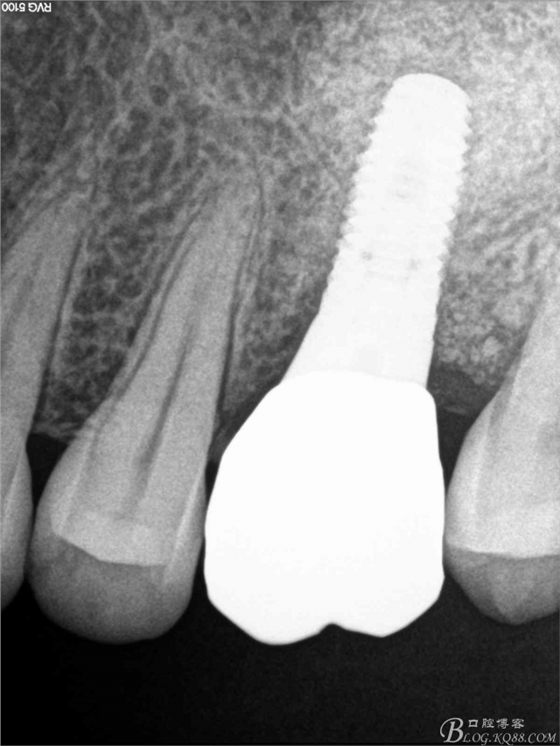

術(shù)后X片。上頜竇外提一例

5個月后X

修復(fù)后X